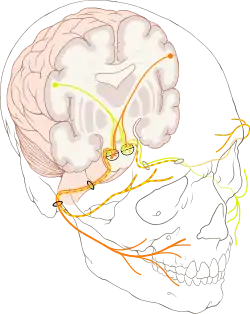

Лицеви́й нерв (лат. nervus facialis), часом трапляється назва промі́жно-лицеви́й нерв (лат. nervus intermediofacialis) — VII пара черепних нервів у людей та решти хребетних[1]. За функцією нерв змішаний: складається з рухових волокон — вісцеромоторних парасимпатичних та спеціальних вісцеромоторних (іннервація м'язів — похідних другої зябрової дуги), та волокон спеціальної (смакової) чутливості[1][2][3]. Також містить невелику кількість волокон загальної чутливості[2][3]. Нерв складається з двох основних структур, які тісно пов'язані між собою під час внутрішньоутробного розвитку та разом формують єдиний нервовий стовбур[1][3]:

Лицевий нерв іннервує всі мімічні м'язи (через що й отримав свою назву — лицевий, тобто пов'язаний з обличчям) та стремінцевий м'яз, забезпечує іннервацією більшість екзокринних залоз голови (слізна залоза, залози слизової оболонки носової та ротової порожнин, слинні залози (окрім привушної), відповідає за смакову чутливість передніх двох третин язика, забезпечує чутливість невеликої ділянки вушної раковини[4]. При ушкодженні нерва виникає його нейропатія (параліч), яка буде проявлятися, залежно від локалізації, випадінням міміки за центральним або периферичним типом, порушенням іннервації екзокринних залоз, гіперакузією, втратою смаку[1][5].

Стовбур мозку та вихід з нього

Рухові волокна, які складають власне лицевий нерв, утворюють петлю довкола ядра відвідного нерва[30]. Волокна, які утворюють цей вигин, відділяють ядро відвідного нерва від четвертого шлуночка і утворюють на ромбоподібній ямці (лат. fossa rhomboidea, ця ямка є дном четвертого шлуночка) лицевий горбок (лат. colliculus facialis)[31]. Окрім вигину довкола ядра відвідного нерва, рухові волокна нерва утворюють ще три вигини: другий опісля того, як обійдуть ядро відвідного нерва, третій, коли проходять під волокнами трійчастого нерва та четвертий, коли оминають середню мозочкову ніжку[32][33]. Лицевий нерв виходить з ділянки мосто-мозочкового кута[1][34] разом із присінково-завитковим нервом[33]. На виході корінці лицевого нерва по суті розділені між двома нервами, які надалі утворять один стовбур: лицевим нервом, який має тільки аксони мотонейронів, та проміжним нервом, що містить чутливі та парасимпатичні волокна. Проміжний нерв розташований між власне лицевим та присінково-завитковим нервами, через що і отримав свою назву. Інколи його також називають нервом Врізберга (таку саму назву має ще й медіальний шкірний нерв плеча)[34]. Лицевий нерв єдиним стовбуром входить у внутрішній слуховий отвір скроневої кістки, через який проходить і присінково-завитковий нерв. Топографічно після виходу зі стовбура мозку лицевий нерв ділять на два великих відрізки[1][34][35]:

Після виходу з каналу

Лицевий нерв покидає лицевий канал через шило-соскоподібний отвір скроневої кістки, пронизує привушну слинну залозу, ділить її на дві частки (поверхнева та глибока) і утворює внутрішньопривушне нервове сплетіння (лат. plexus intraparotideus). Всі гілки, що відходять від цього місця є виключно руховими[37]: